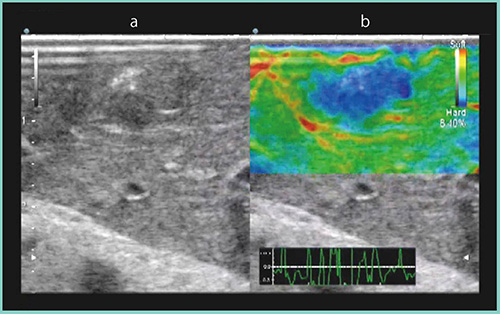

症例1は,大腸がんの肝転移でS3表面に病変がある症例である。RTEで,画面下部に表示されるインジケータを参考に適切な圧でプローブを当てると,病変は硬い腫瘍として青く表示された(図1b)。

図1 症例1:肝転移切除(S3)のRTE